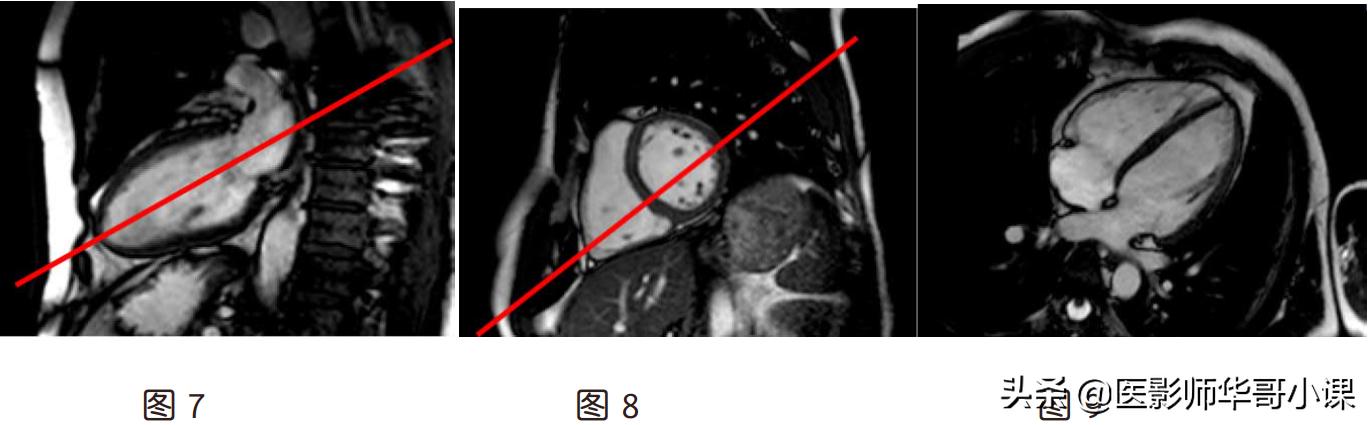

(3)四腔心(图 9):假两腔心上(图 7)定位线平行心尖到二尖瓣中点连线,左室乳头肌

肉层面短轴位(图 8)上平行左室中心到右室口的连线

(4)左两腔(图 12):左室乳头肌层面的短轴位(图 10)上定位线通过左室中心并与室间

隔平行,四腔心上(图 11)平行心尖到二尖瓣口中点的连线